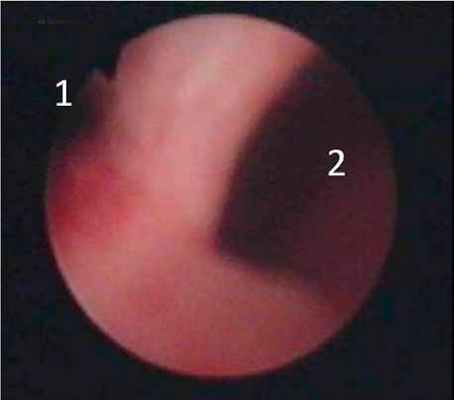

16.07.2007 г. выполнена уретроцистоскопия, при которой в средней трети уретры определяется дивертикул с устьем 0,5 см (рисунок 4).

| Рисунок 4. Уретроцистоскопия. 1 – ход уретры. 2 – устье дивертикула. |

Инструмент с техническими сложностями проведен в полость дивертикула. Слизистая дивертикула гиперемирована с единичными петехиальными кровоизлияниями. При осмотре мочевого пузыря: емкость - около 400 мл, устья мочеточников расположены в типичном месте, смыкаются, перистальтируют, умеренная гиперемия слизистой в области треугольника Льето. В полости мочевого пузыря конкрементов, объемных образований не выявлено.